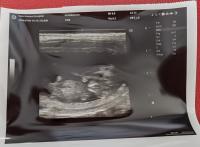

エレナ出産前の頭数確認にレントゲン検査行ってきました、6頭の天使達が確認できました❣

エレナ受胎していました!

エレナ&ディランの交配成功で受胎していました!エレナとディランの子はみんな派手で可愛い子達が生まれます!

エコー検査で6頭位天使達がいるとのことでした、今月末か来月初め出産予定です~みんな無事に生まれてきますように。